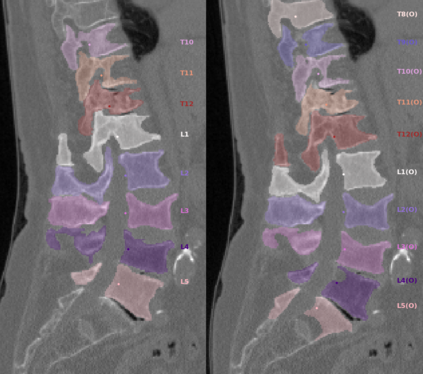

Vertebrae localization, segmentation and identification in CT images is key to numerous clinical applications. While deep learning strategies have brought to this field significant improvements over recent years, transitional and pathological vertebrae are still plaguing most existing approaches as a consequence of their poor representation in training datasets. Alternatively, proposed non-learning based methods take benefit of prior knowledge to handle such particular cases. In this work we propose to combine both strategies. To this purpose we introduce an iterative cycle in which individual vertebrae are recursively localized, segmented and identified using deep-networks, while anatomic consistency is enforced using statistical priors. In this strategy, the transitional vertebrae identification is handled by encoding their configurations in a graphical model that aggregates local deep-network predictions into an anatomically consistent final result. Our approach achieves state-of-the-art results on the VerSe20 challenge benchmark, and outperforms all methods on transitional vertebrae as well as the generalization to the VerSe19 challenge benchmark. Furthermore, our method can detect and report inconsistent spine regions that do not satisfy the anatomic consistency priors. Our code and model are openly available for research purposes.